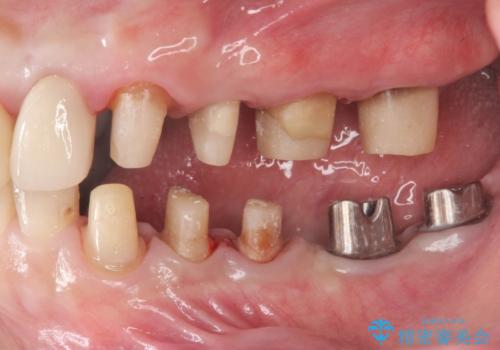

銀歯を外し、インプラントを入れたい

- 「治療途中の歯を治したい。この際、銀歯も全て外したい。インプラントも入れてしっかり噛めるようにしたい。徹底的に歯の治療をしたい。」

と総合的な治療を希望され来院されました。

ここの歯の状態を精密に検査し、根管治療、セラミック治療、インプラント治療を含む総合的な歯科治療を計画します。

部分的な治療ではなく、全体的な治療を任せていただけたことで、清掃性の高く咬合関係の良い治療を行うことができました。

見た目の改善だけでなく、噛み合わせの仕上がりにも大変満足いただくことができました。